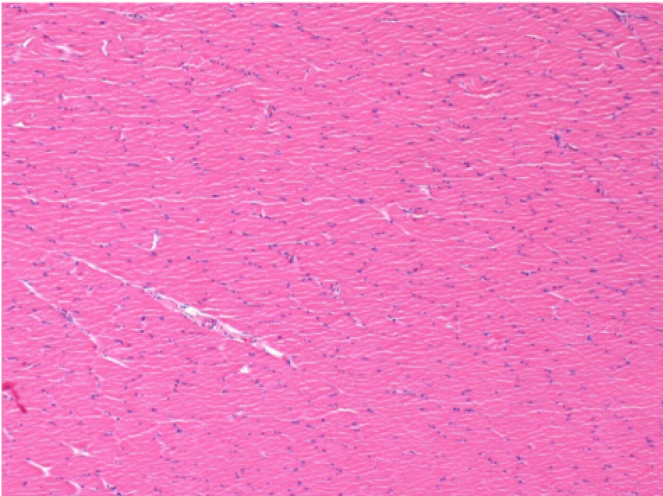

1 month after Endopeel Injection 0.1ml in the right pretibial muscle.

What is seen in black on the pictures is not a necrosis like could imagine some scientifics !

In fact, 4 conclusions have to be taken in consideration